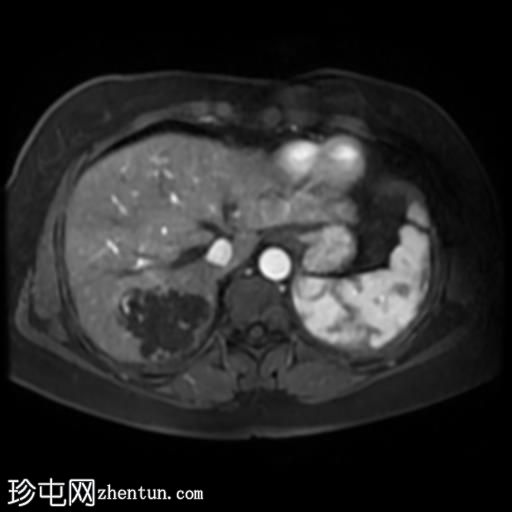

轴位T1加权像增强扫描

脂肪抑制动态增强扫描

肝脏第7段可见一边界清晰的分叶状肿块。T1加权像呈低信号,T2/T2脂肪抑制序列呈高信号,动脉期呈不连续结节状周边强化,门静脉期呈向心性强化,延迟期完全强化。DWI序列呈高信号,ADC值呈混合信号。